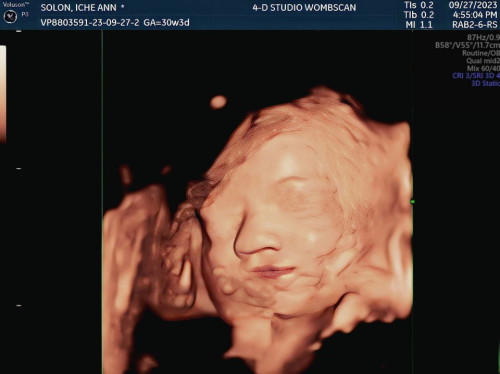

4-D ULTRASOUND

Hello mga mommies share ko lang 4-D ult ni baby girl namin. Nakakaiyak walang nakuha saken 😂 yung feeling na ikaw ang naghirap tapos magmamana lang sa daddy 🥹🤣